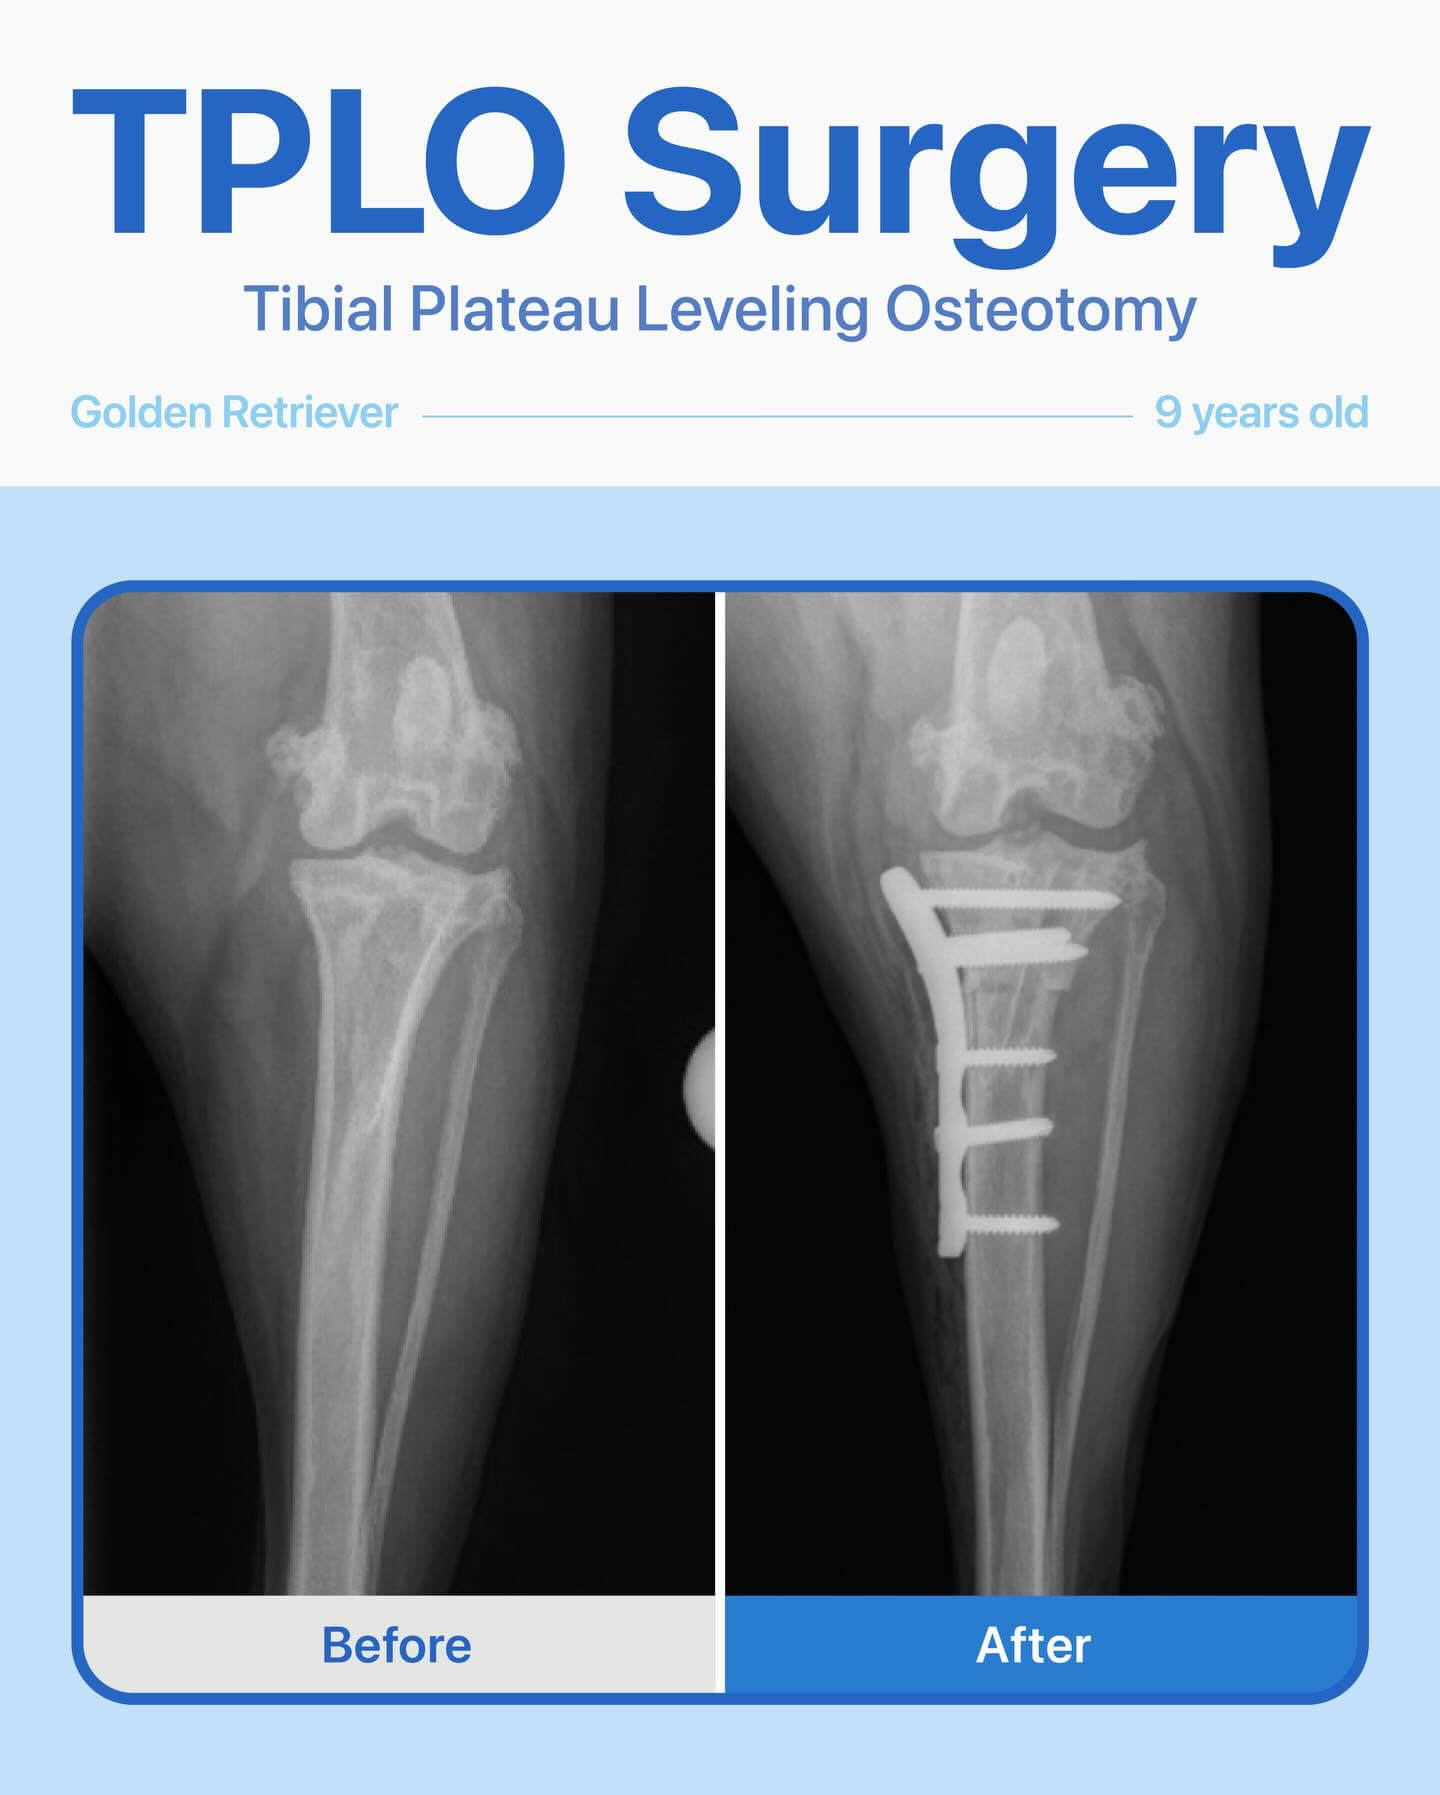

After a thorough orthopedic exam and radiographs, we diagnosed a cranial cruciate ligament tear and recommended TPLO (Tibial Plateau Leveling Osteotomy) surgery to restore stability and comfort.

We’re happy to share that her surgery went smoothly and successfully! She has been recovering beautifully and is healing very well. Watching her regain comfort and mobility is the best reward.